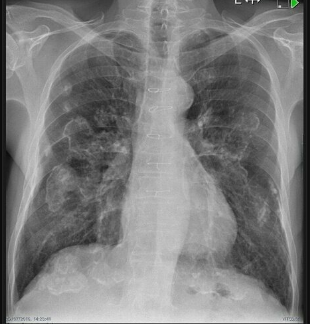

The following CXR is highly suggestive of what pulmonary pathology? _____